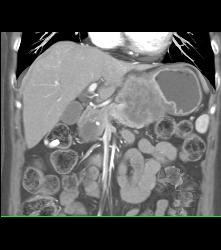

Antral Carcinoma With Celiac and Peri-portal Nodes